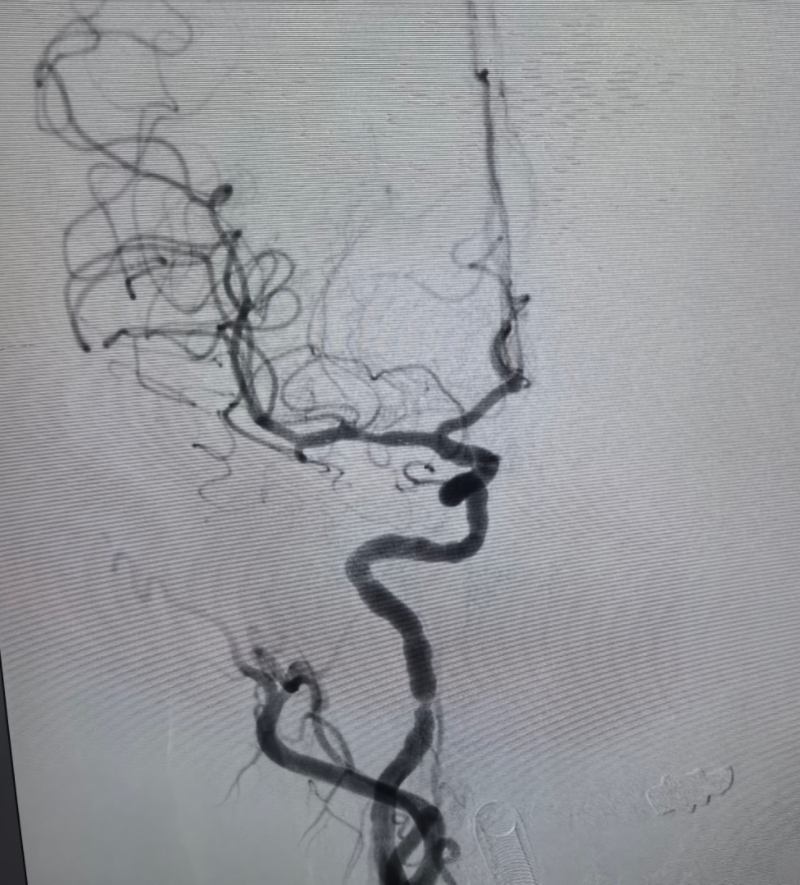

但仍面临极高的复发风险。进一步完善 CTP(计算机断层扫描灌注成像)、DSA(数字减影血管造影)及核磁共振管壁成像等检查后,明确诊断为 “大脑中动脉重度狭窄次全闭塞(动脉粥样硬化性)”。据神经内科主任陈国芳主任及神经血管介入傅新民主任团队评估,患者血管狭窄程度重,斑块不稳定,随时可能再次发生大面积脑梗死,不仅可能导致肢体瘫痪、失语等严重致残后果,更可能危及生命,手术治疗刻不容缓。

术前,影像科师毅冰主任团队已完成精准筛查,为手术方案制定提供了详实的影像学依据;手术当日,神经血管介入MDT团队傅新民主任凭借丰富的临床经验和精湛的操作技术,由导管室护士长张学萍安排手术间、朱春婷导管室护师精心协助下,历时 1 小时完成精准治疗 —— 先以小球囊对狭窄血管段进行逐步扩张,再成功释放颅内支架,全程操作规范、精准高效,最大限度保护了患者正常脑组织供血。